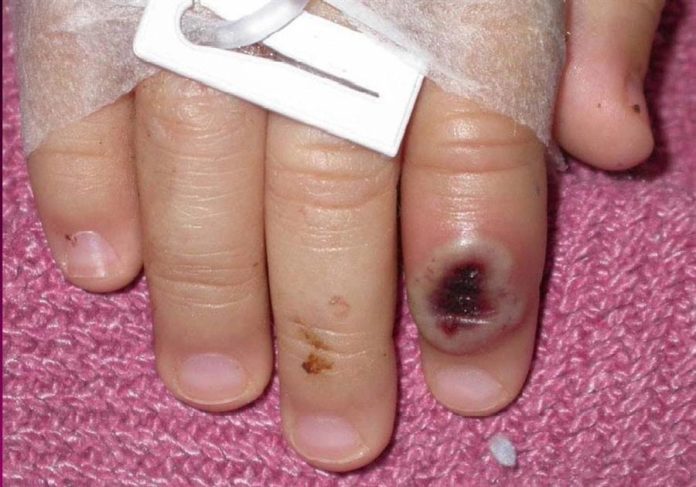

Los síntomas de la viruela del mono son similares a la de la ya erradicada viruela, aunque algo más leves – fiebre, dolor de cabeza, muscular, de espalda, escalofríos y agotamiento- y con frecuencia hay inflamación de los ganglios y una erupción cutanea, que comienza en la cara y se extiende a otras partes del cuerpo, principalmente manos y pies.